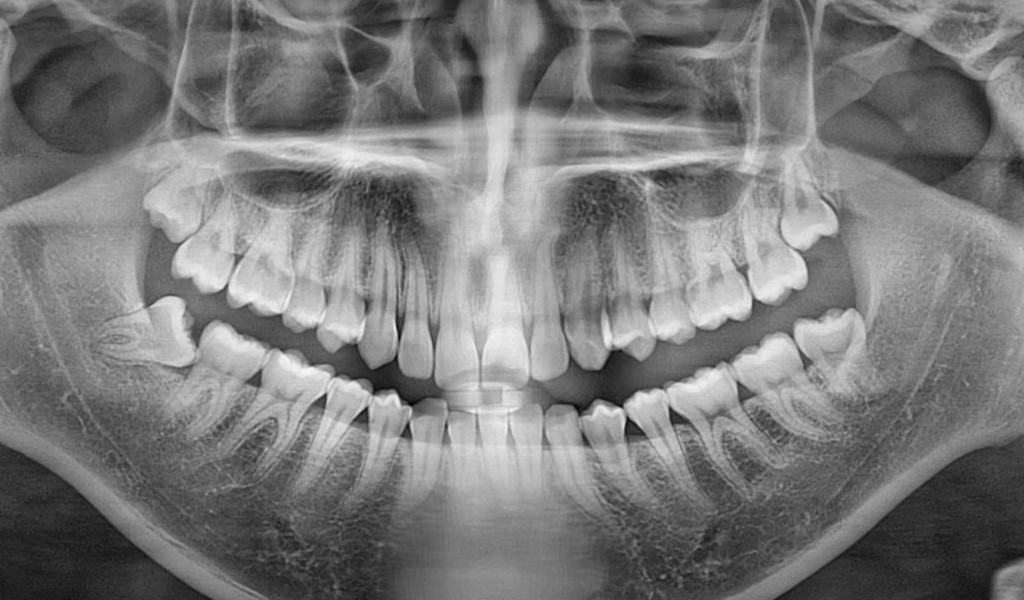

- 사랑니는 17세~25세 무렵 맹출하는 제3대구치입니다.

- 보통 상·하악 구치부 맨 뒤쪽에서 나며, 총 4개가 날 수 있습니다.

- 하지만 턱뼈 공간 부족으로 정상적으로 나오지 못해 **매복치(Impacted tooth)**가 되는 경우가 흔합니다.